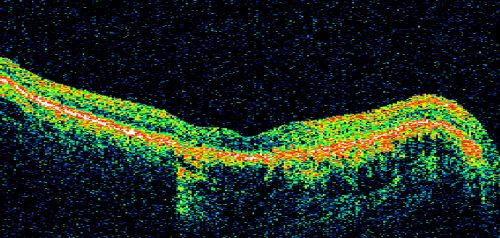

Geographic Atrophy and Age-Related Macular Degeneration - Choriocapillaris is Largely Still Intact

85-year-old woman has age-related macular degeneration in both eyes with geographic atrophy.  She has noticed her vision getting slightly worse in the past 6 months. VISUAL ACUITY:  OD 20/70, OS 20/400